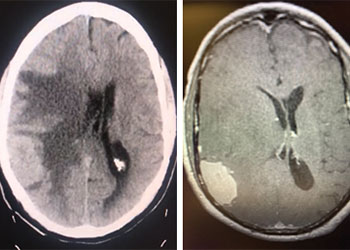

Cerebral Metastases from Non-Small Cell Lung Cancer

Author: Xavier P. J. Gaudin D.O., F.A.C.O.S., Read More!